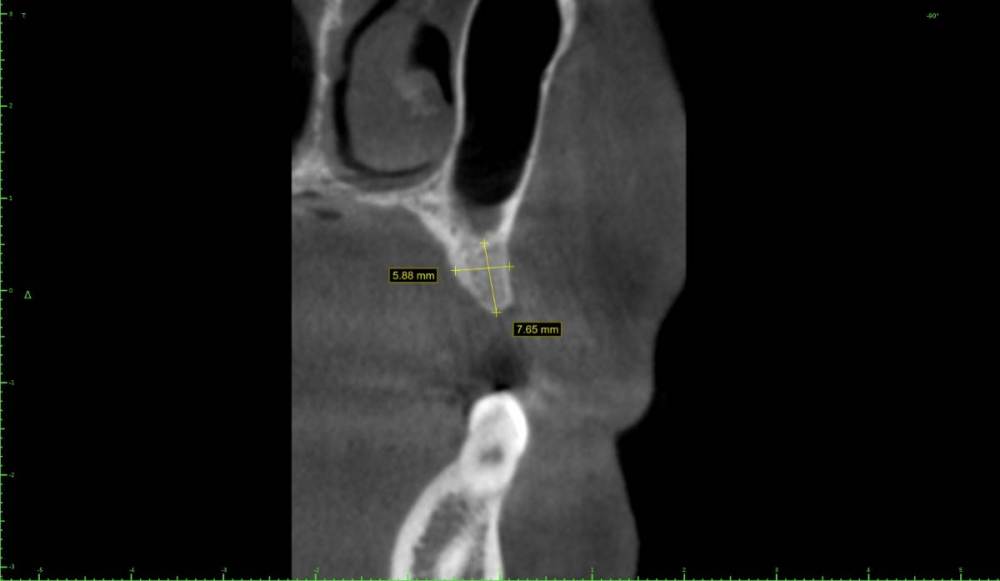

Женька Опубликовано 27 марта, 2021 Поделиться Опубликовано 27 марта, 2021 Коллеги, всегда задаюсь вопросом что делать в таких случаях? Пока никак сам не решал, потому что пациенты отказываются в пользу мостовидных и съёмных конструкций. Мини сосиска и и имплантат отсрочено с "мягким" синусом? Ссылка на комментарий